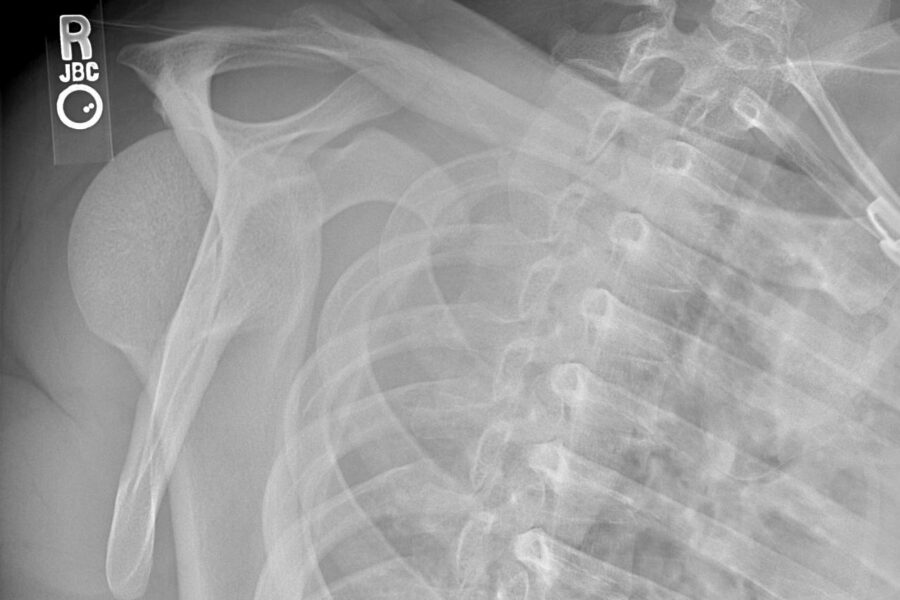

The CASE A 52 yo patient presents following a fall onto the right outstretched hand.…